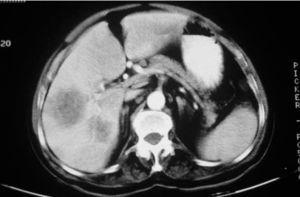

Fig. 2.—TC abdominal con lesiones redondeadas hipodensas en el hígado compatibles con abscesos.

A pesar de la mejoría del pioderma, el paciente empezó a presentar fiebre vespertina, astenia y anorexia, y acudió en varias ocasiones a urgencias, por lo que fue ingresado en abril de 1999. Se constató un importante cuadro tóxico general con fiebre persistente y dolores musculoesqueléticos generalizados. En la exploración presentaba una paroniquia purulenta en el segundo dedo de la mano derecha, cuyo cultivo fue negativo. En la analítica general destacaba una leucocitosis con neutrofilia, unos reactantes de fase aguda muy elevados, con una velocidad de sedimentación globular (VSG) superior a 130 mm/h y una proteína C reactiva (PCR) de 25 (normal, 0,1-0,5 mg/dl). En la bioquímica destacaban una transaminasa glutamicooxalacética (GOT) de 60 U/l (normal, < 38 U/l), transaminasa glutamicopirúvica (GPT) de 149 (normal, < 42 U/l), gammaglutamiltranspeptidasa de 149 (normal, < 66 U/l) y fosfatasa alcalina de 294 (< 129 U/l); posteriormente aparecieron hipoproteinemia progresiva y anemia que requirió varias transfusiones. Una tomografía computa-rizada (TC) abdominal demostró la presencia de numerosas lesiones ocupantes de espacio en el hígado y el bazo (fig. 2). Se suspendió la ciclosporina A y se practicaron numerosos cultivos, tanto de sangre como de varias punciones hepáticas, que fueron siempre negativos para bacterias, hongos y micobacterias. Se instauró antibioticoterapia parenteral de amplio espectro durante 4 semanas con piperacilina, tazobactam y clindamicina, con mejorías transitorias tanto en la práctica clínica como en la TC abdominal. El paciente reingresó a los 15 días del alta por la misma sintomatología de fiebre, dolor abdominal y osteomuscular, con un cuadro tóxico grave, anemia y pérdida de 13 kg de peso desde el inicio del proceso. En la TC abdominal se constató la persistencia de pequeñas lesiones hipodensas en el hígado de 1-2 cm de diámetro y en el bazo tres lesiones, la mayor de 1,5 cm, compatibles radiológicamente con abscesos. El paciente presentó además una artritis fluctuante de la articulación esternoclavicular derecha, que se drenó con estudio microbiológico negativo, así como lo fueron varios hemocultivos y una punción esplénica. Se reinició antibioticoterapia oral con clindamicina y ciprofloxacino, que completó durante 2 meses en su domicilio. A pesar de ello se presentaron episodios febriles, con una VSG muy elevada de 135 mm/h, una PCR de 25,2 mg/dl con leucocitosis (20.800/l) y neutrofilia. En febrero de 2000 y ante la persistencia de la fiebre y al existir en ese momento sólo abscesos en el bazo, se decidió realizar una esplenectomía (fig. 3), a pesar de lo cual persistió el cuadro febril. Se retiraron los antibióticos y se inició tratamiento con prednisona oral (40 mg/día) y sulfona (100 mg/día) con rápida mejoría del estado general, desaparición de la fiebre y la VSG se normalizó al mes de iniciarse el tratamiento. El paciente ha ido siguiendo una pauta decreciente de esteroides orales manteniéndose la sulfona oral, a lo largo de los 3 últimos años. Actualmente el paciente sigue asintomático, bajo un régimen terapéutico de azatioprina 50-100 mg/día y sulfona 100 mg/día.